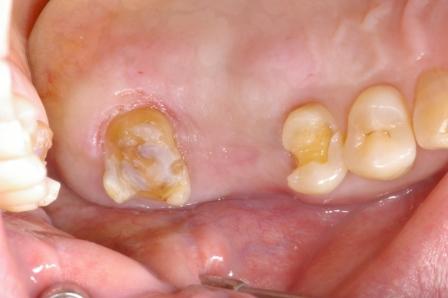

続いて奥歯のブリッジの症例です。

奥歯の2本を土台にしてブリッジを入れました。歯のないところにはブリッジを入れる治療が現在までの主流でした。

ただし、歯のないところにインプラント(人工の歯根)を植えると、土台の歯は削らないですみます。